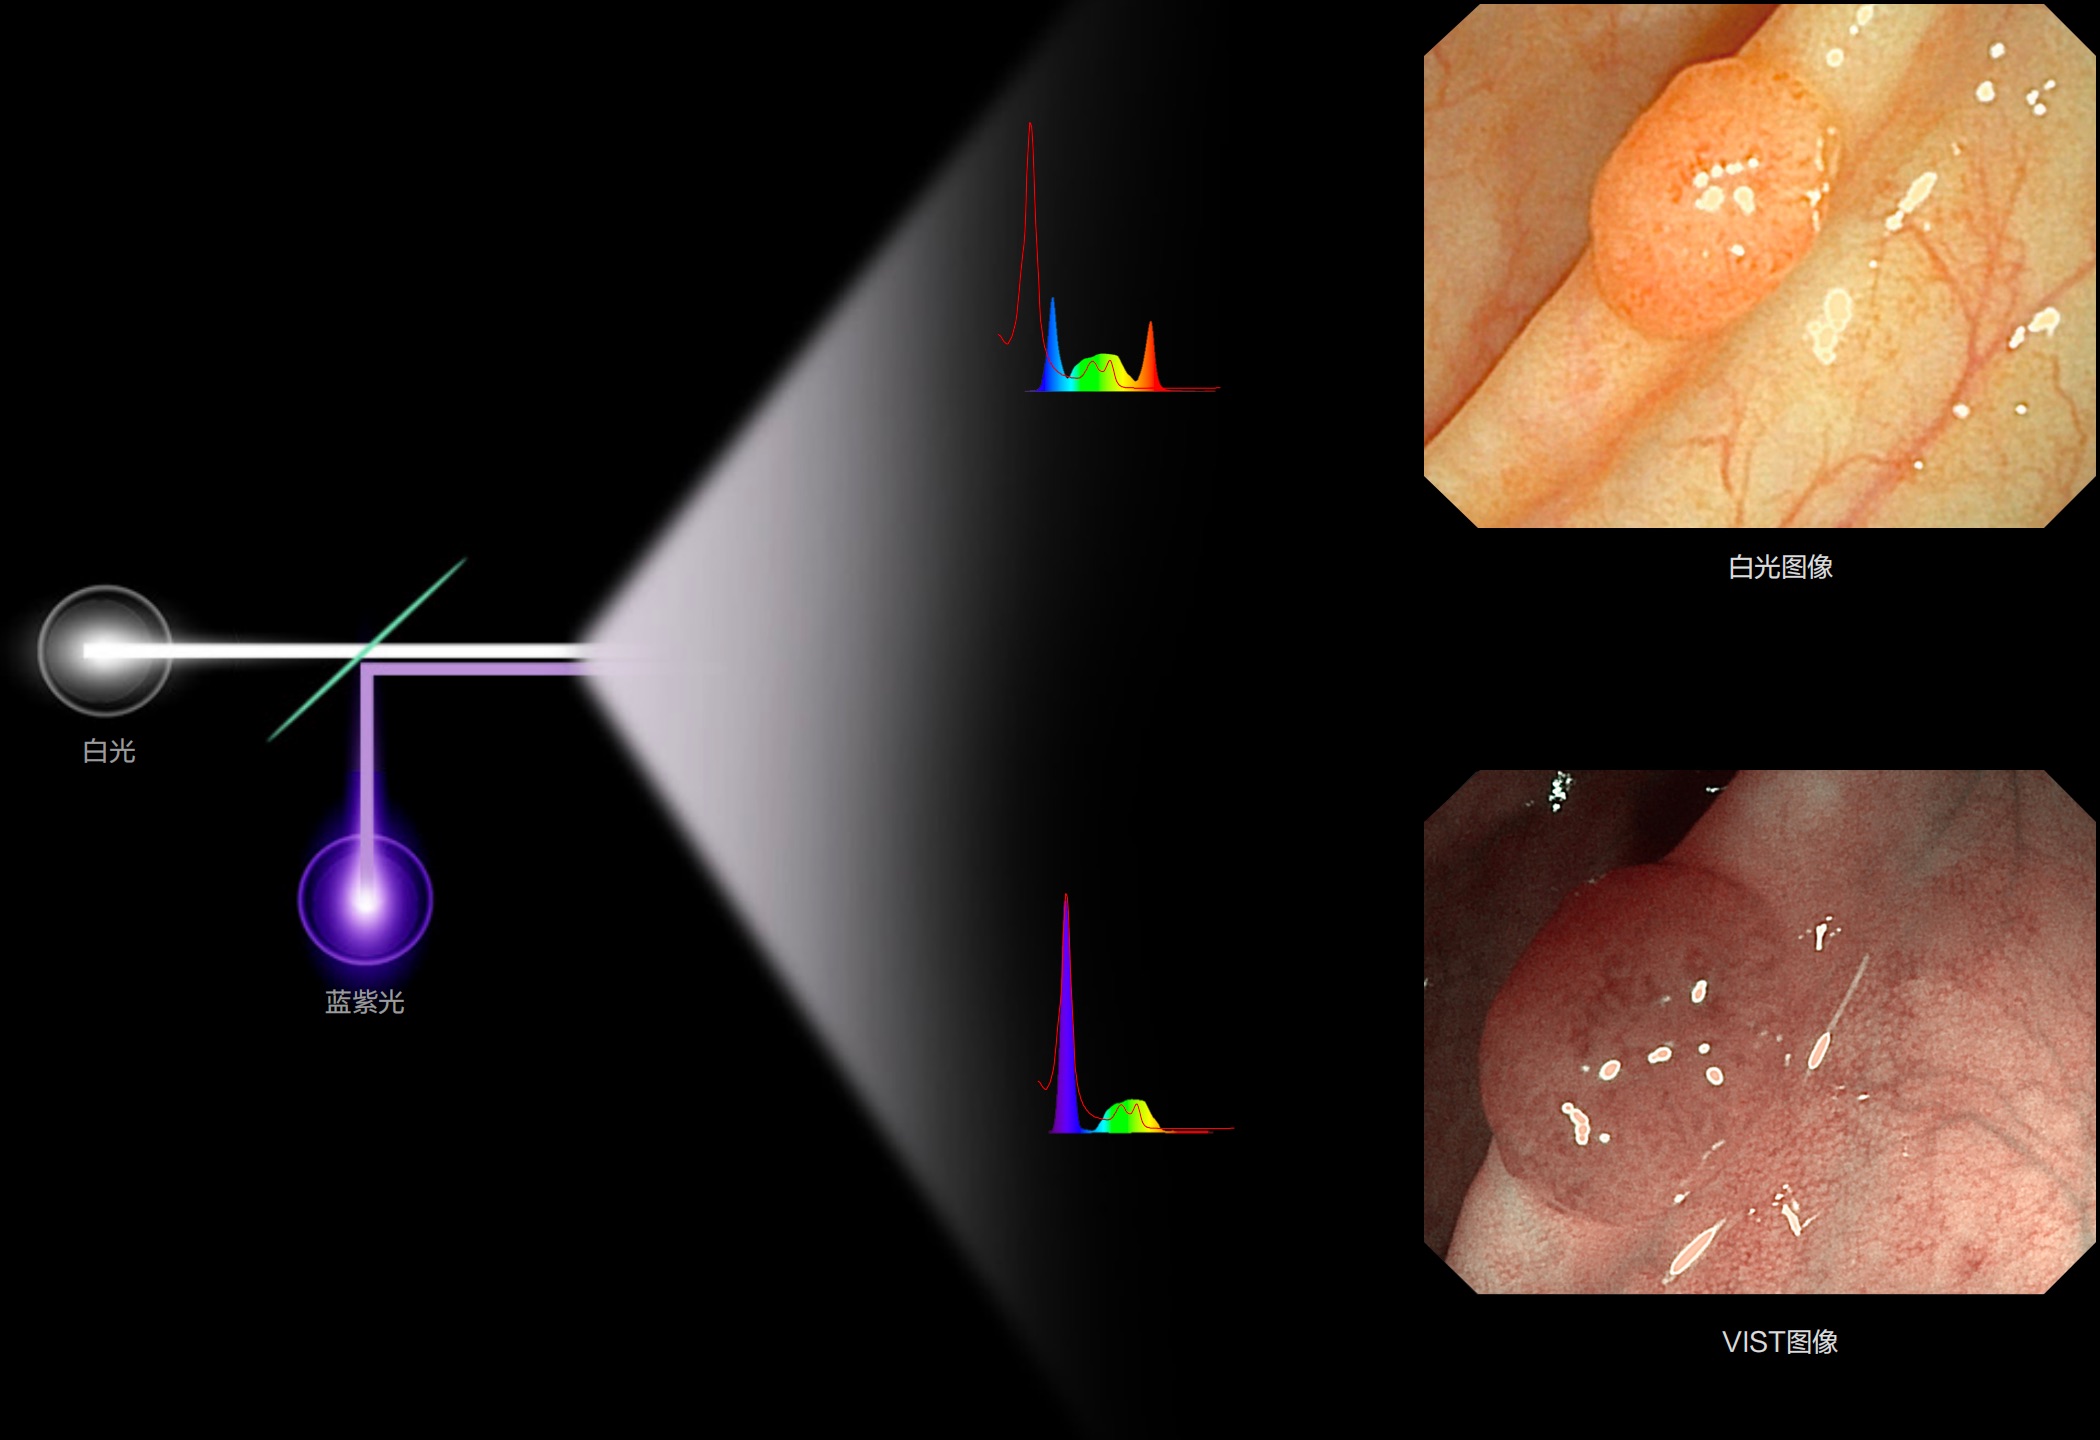

(Versatile Intelligent Staining Technology)

能够凸显黏膜浅层血管轮廓和黏膜表面微结构,适用于中、近景观察下的早癌精确诊断。